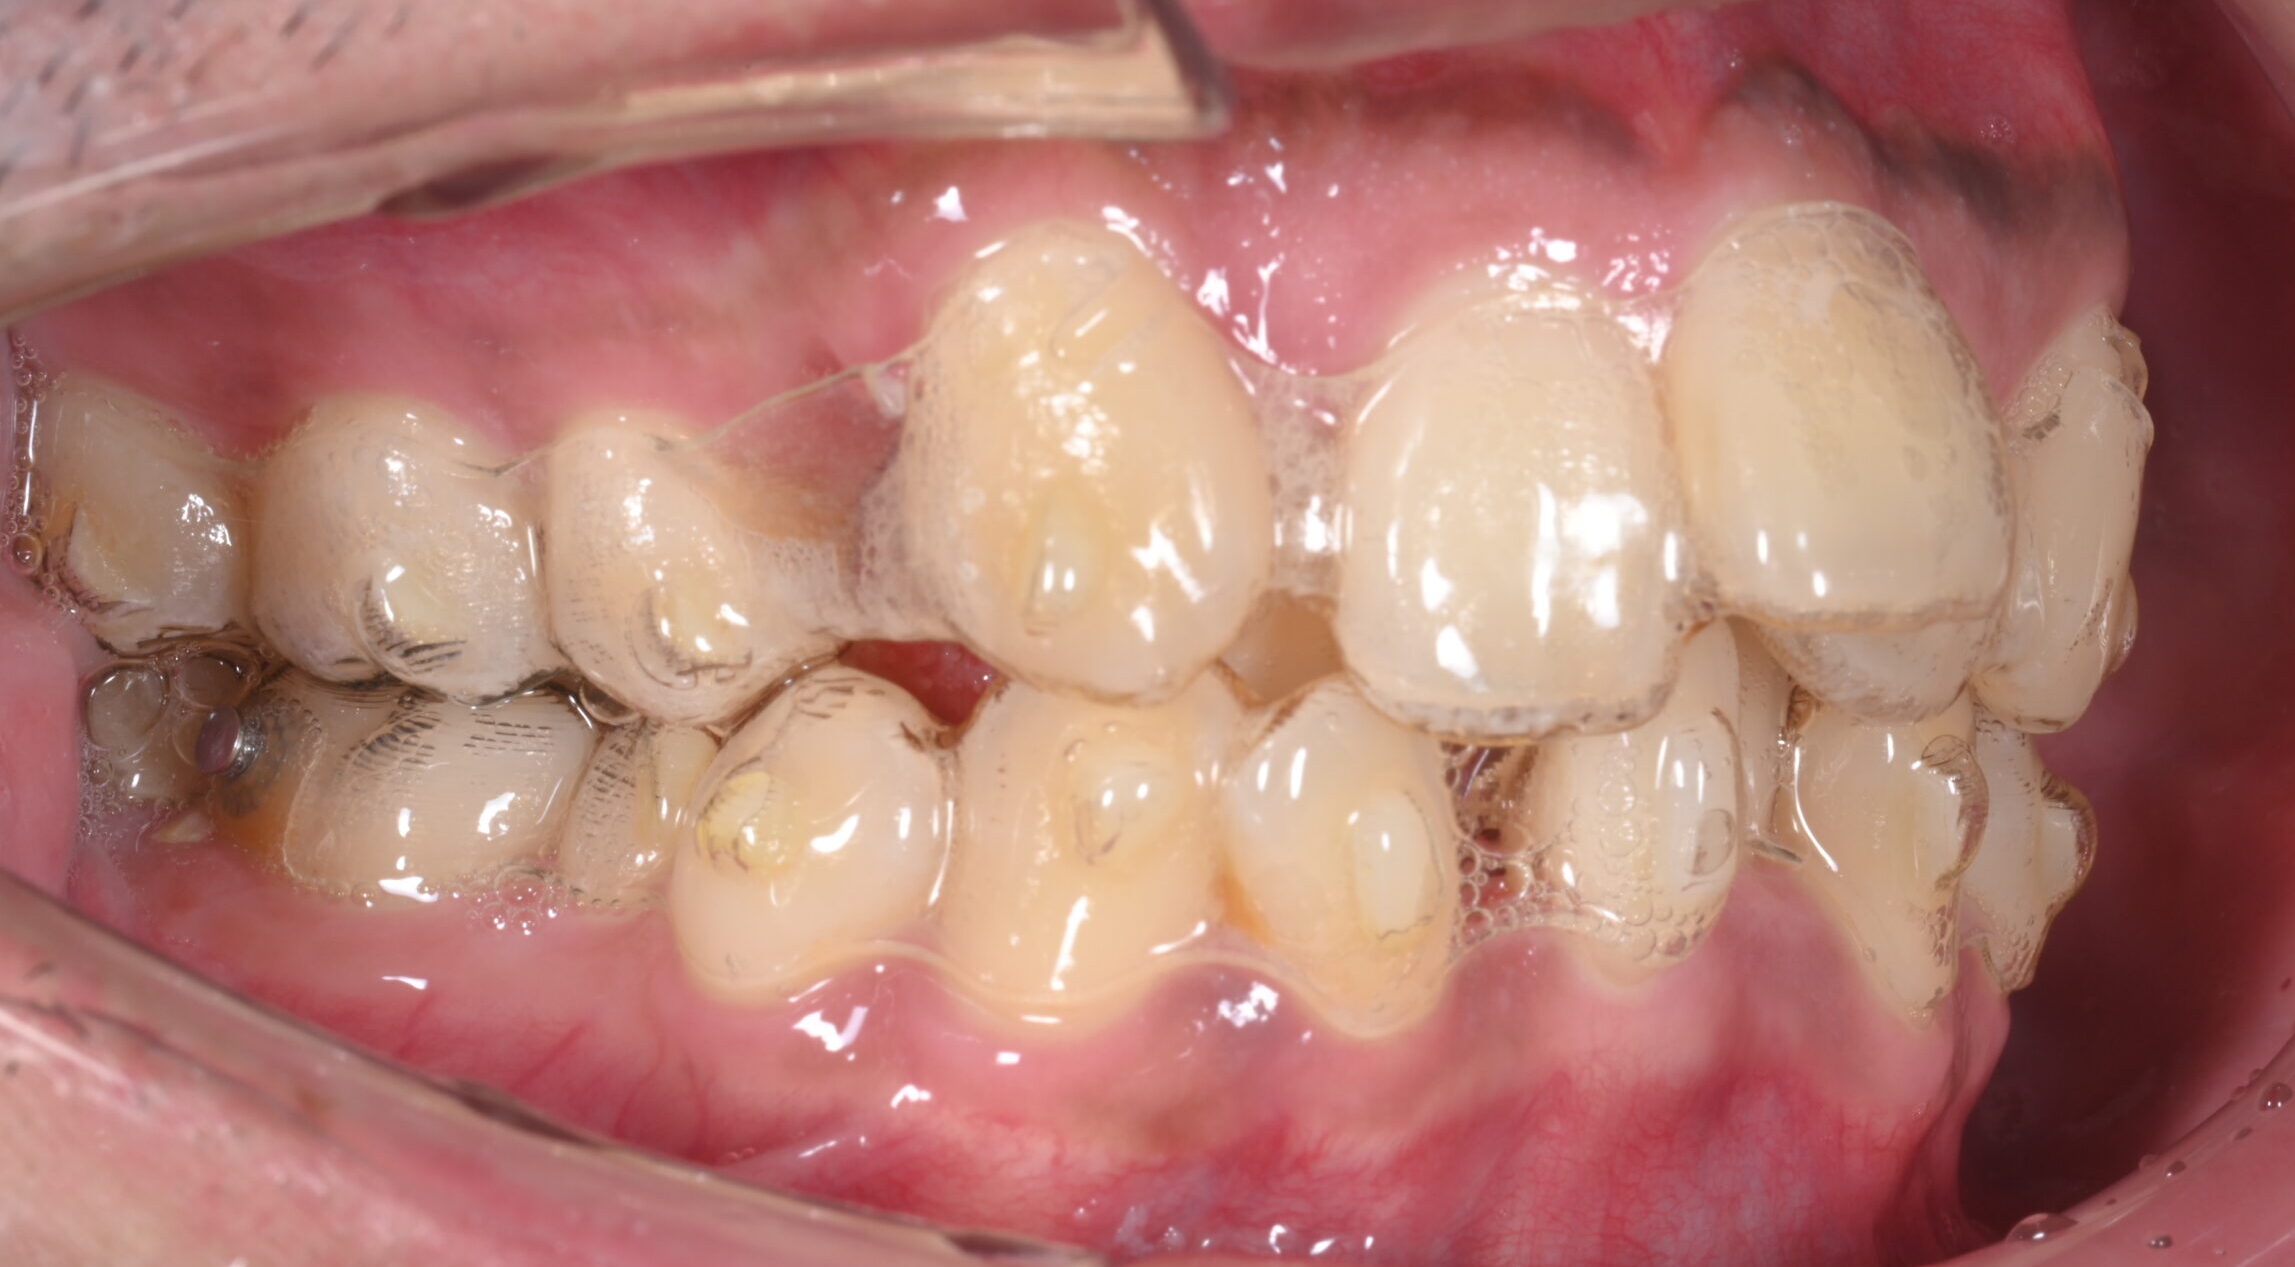

《初診時》

患者様の主訴は叢生、いわゆる歯のガタガタでご来院されました。

この写真のように歯に目立たない透明なマウスピースを装着して矯正行っていきます。